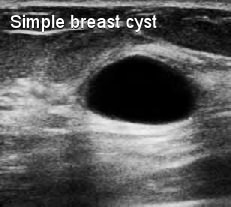

Kista payudara adalah kantung berisi cairan di dalam jaringan payudara dan akan muncul sebagai benjolan payudara. Baik kista payudara maupun penyakit payudara fibrokistik adalah lesi jinak dan tidak berkembang menjadi kanker payudara dan tidak meningkatkan risiko kanker.

Kista payudara yang kompleks yang mengandung campuran jaringan padat di dalam kista payudara mungkin memiliki risiko perubahan ganas, oleh karena itu perlu diselidiki dan dipantau.

Kista payudara yang kompleks

Skrining payudara secara teratur dengan MMG dan USG payudara untuk menyingkirkan benjolan kanker yang mencurigakan